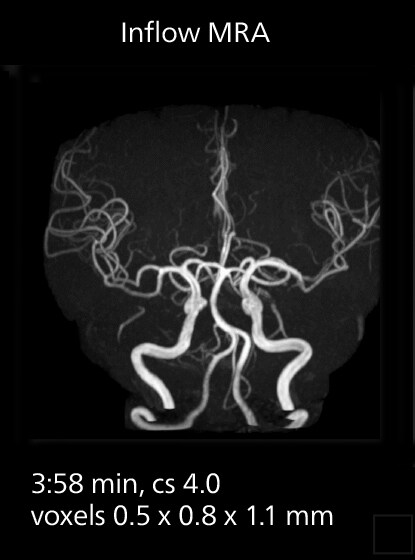

These images of an old cerebral infarction demonstrate the speed and image quality after upgrading to Elition X.